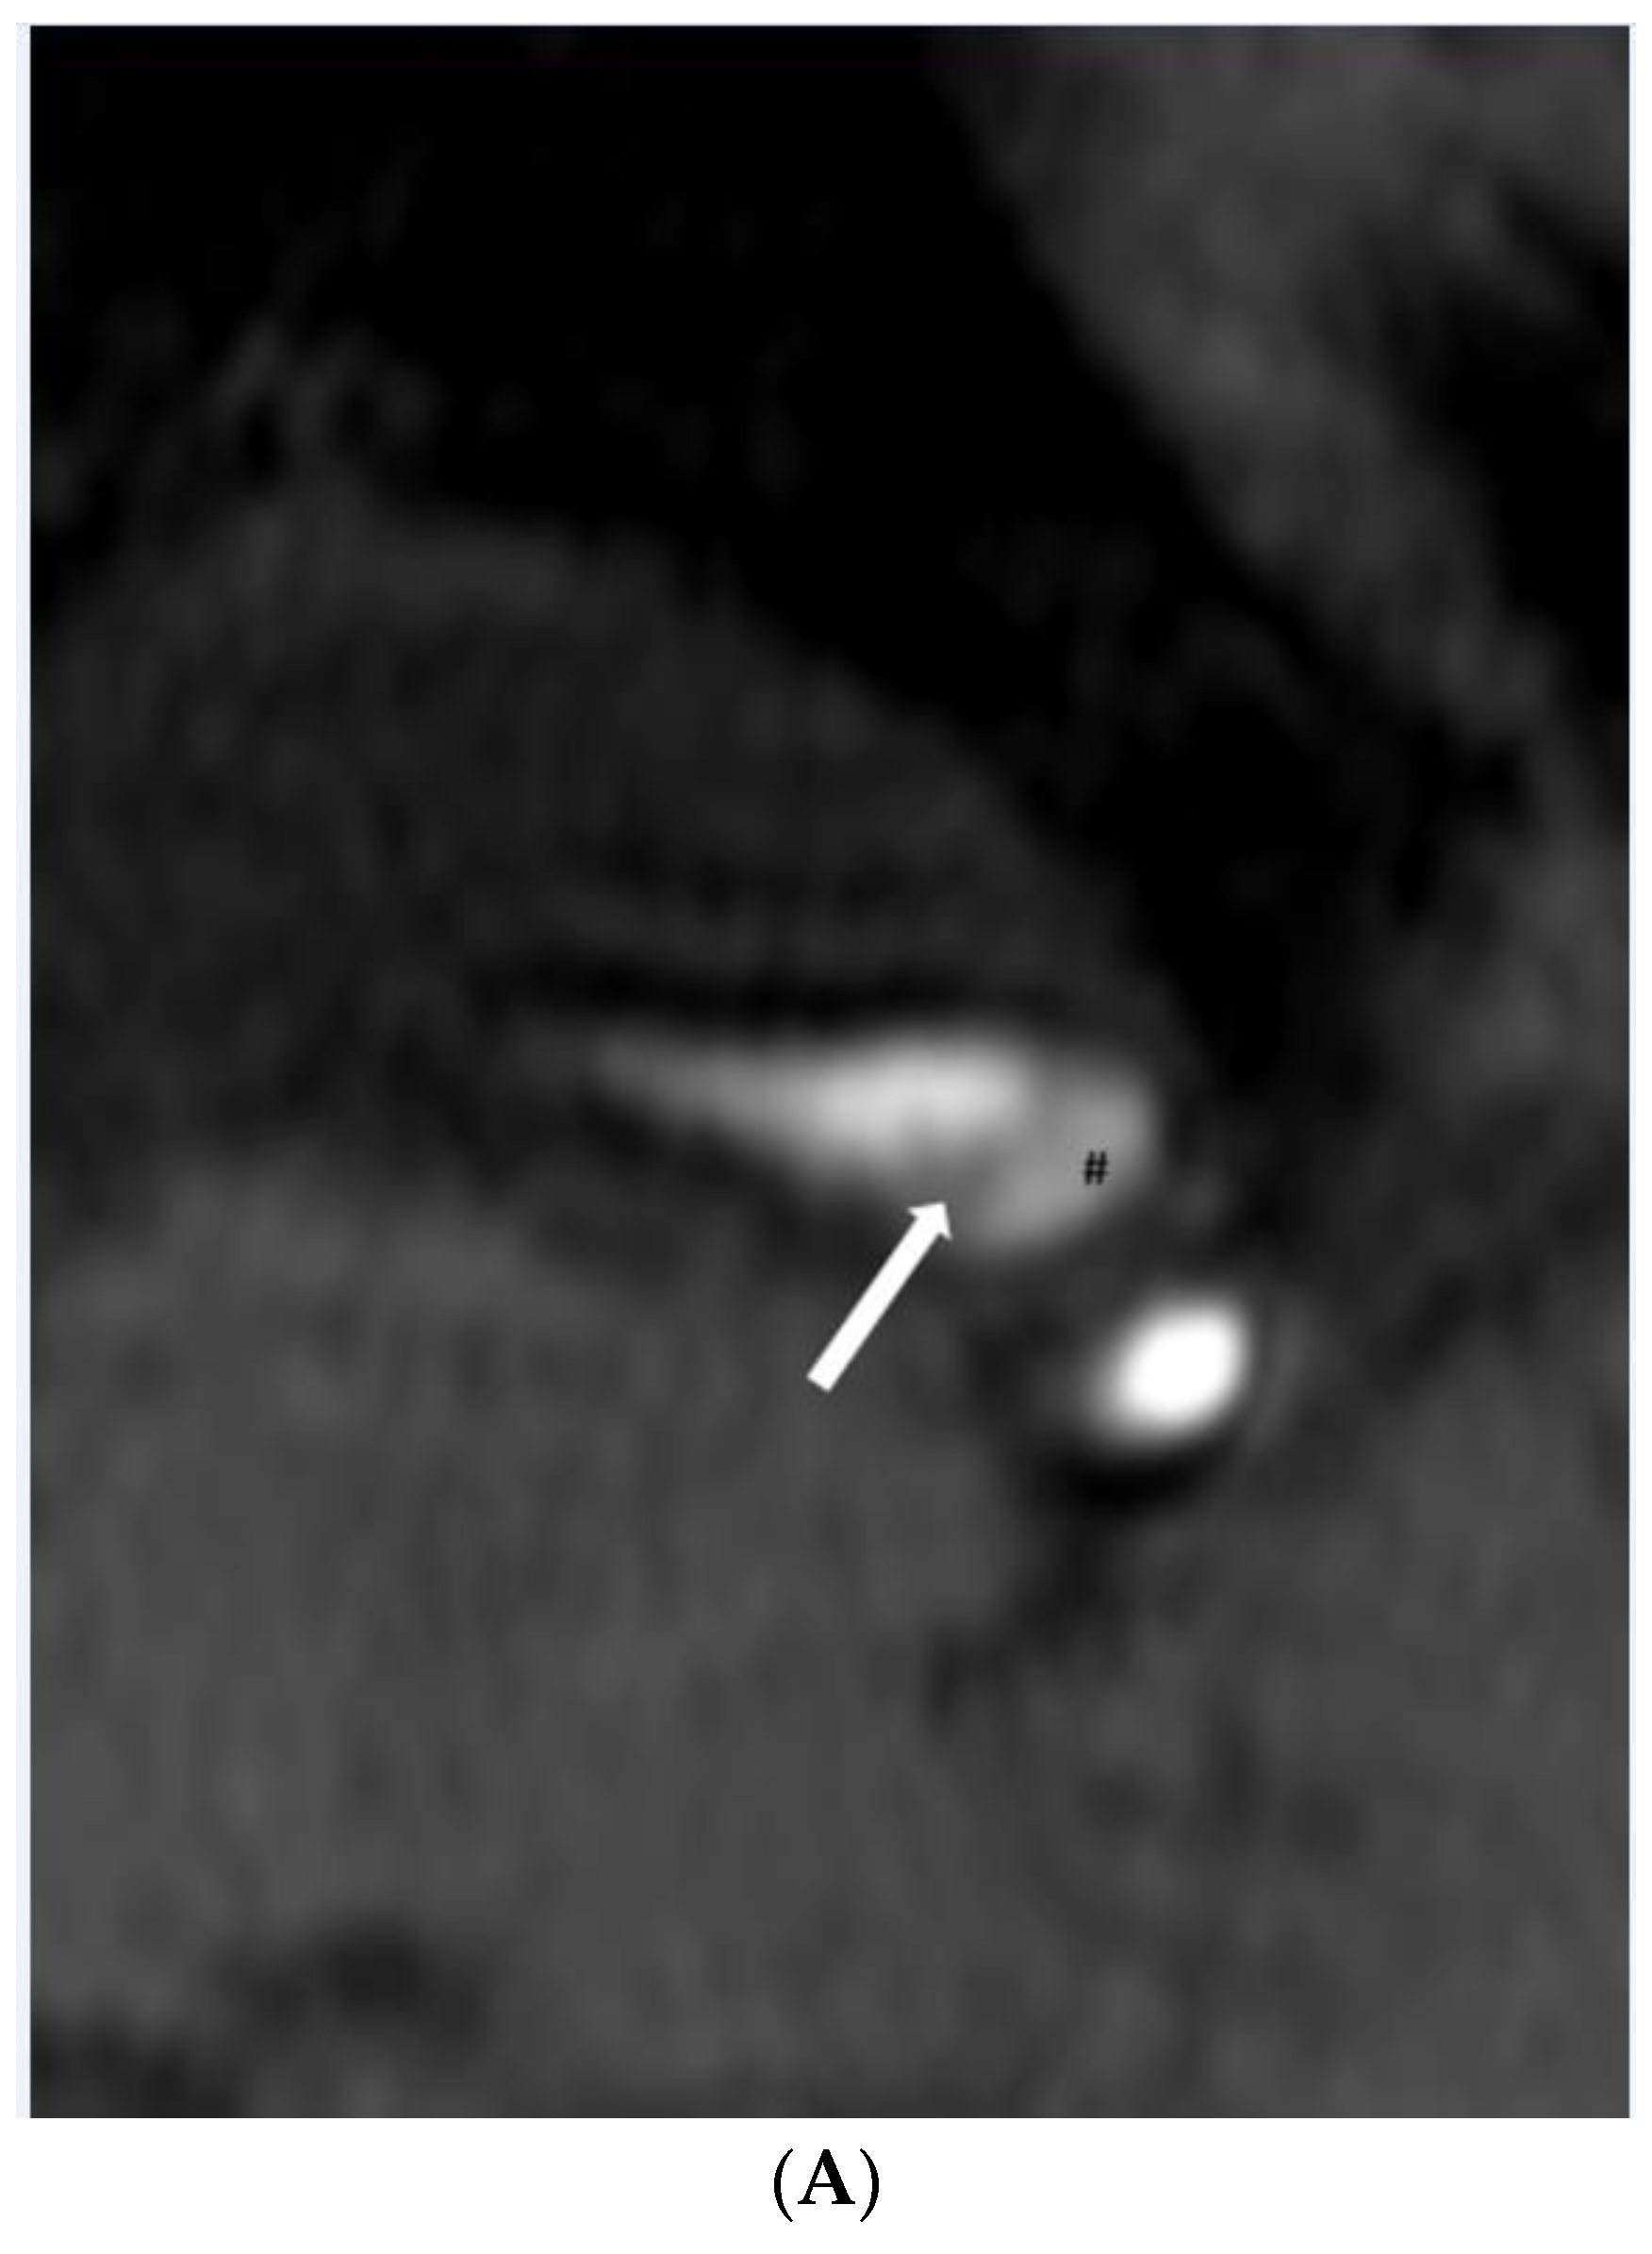

3. Results